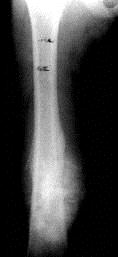

问题 病历摘要: 患者 ×××,男性,9岁,右大腿下段肿痛3个月。查体:T 36.7℃, P 80次/分,右大腿下段皮肤肿胀,血管恕张,触痛(+),质硬,叩击痛(+),其余(-)。实验室检查:ESR 20mm/L。 该患儿最有可能的诊断是? 提示:该患儿 X线片如图:

选项 A、右股骨骨质旁肉瘤 B、右股骨尤因肉瘤 C、右大腿横纹肌肉瘤 D、右大腿恶性纤维组织细胞瘤 E、右股骨骨巨细胞瘤 F、右股骨骨髓炎 G、右股骨成骨肉瘤

答案 G